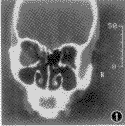

1997年2月~1999年2月共收治眶壁击出性骨折8例,其中单纯纸板骨折6例,均系眶部拳击伤所致,伤后均出现眶区明显肿胀及眼球挫伤,其中伴有眼前房出血4例次,虹膜根部断裂1例次,视网膜出血2例次,无颅脑及其它重要脏器损伤。全部病例均初治于眼科,伤后15 d ~2个月出现眼球凹陷,睑裂变小及复视等症状。患者至我科就诊时间为伤后1~6.5个月,外伤至手术治疗时间为1.5~7个月。眶部CT(水平+冠状)扫描均示纸板骨折,眶内容疝入筛窦内,眼球结构未见异常。为了解骨折的范围及程度,以CT片所示的纸板骨折缘及其连线作为基线,测得骨折位移程度为5~8 mm,由水平位测得骨折前后径(水平径)为23~32 mm, 由冠状位测得骨折上下径(垂直径)为10~22 mm(图1,2)。眼球凹陷程度3~6 mm,平均4.2 mm。复视出现率66.6%(4/6)。症状均呈晨轻、午后重的规律变化。

图1,2 术前眶部CT示纸板骨折,眶容突入左侧筛窦,以纸板上下、前后骨折缘及连线为基线,可测得骨折的位移程度及范围。(冠状位、水平位)